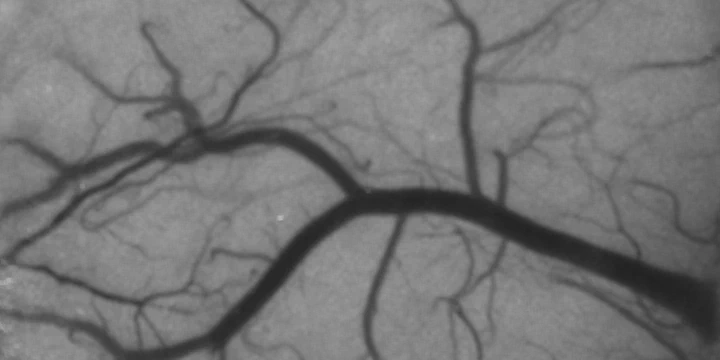

Speckle contrast image of cortical blood flow (Sullender, 2022)There has been increasing interest in using laser speckle contrast imaging (LSCI) as a tool for imaging blood flow in preclinical research and clinical applications. LSCI utilizes intrinsic tissue contrast from dynamic light scattering to offer a relatively simple technique for visualizing detailed spatiotemporal dynamics of blood flow changes in real-time.

Laser speckle is the random interference pattern produced when coherent light scatters from a medium that can be imaged onto a detector such as a camera. Motion from scattering particles, such as red blood cells in the vasculature, leads to spatial and temporal variations in the speckle pattern. Speckle contrast analysis quantifies the local spatial variance ($K$), or blurring, of the speckle pattern that results from blood flow.

Areas with greater motion have more rapid intensity fluctuations and therefore more blurring of the speckle pattern during the camera exposure (Fig. 1). LSCI can be used to quantify relative changes in blood flow, and has been studied both in animal models and in the clinic.